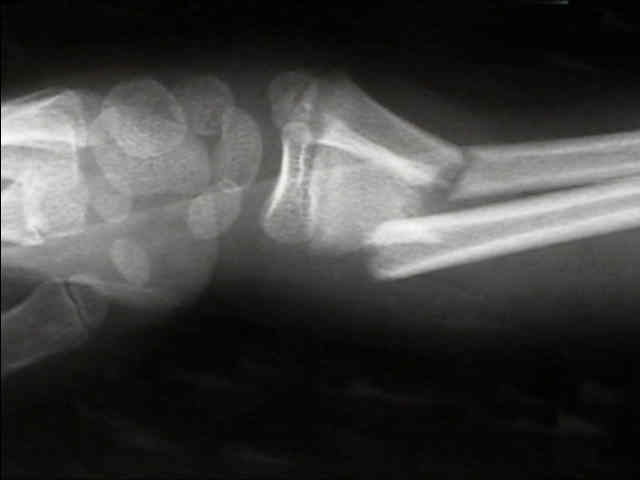

Displaced Distal Third Frx

- angulation up to 20-25 deg during first ten years is OK;

- angulation > 10 deg is unlikely to correct after 10 yrs